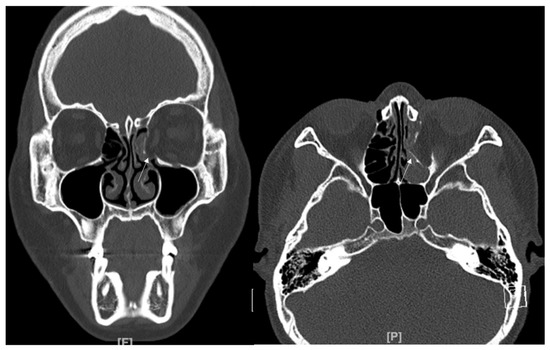

In this study, we excluded inferior wall fracture involving IOS. However, as shown in Figure 8, this inferior wall fracture with the involvement of IOS is also a good candidate for using titanium-reinforced porous polyethylene (TR-PPE) plates.

Figure 8. (A) A 29-year-old male patient came to our clinic with right eyeball swelling and ecchymosis caused by a direct trauma. The patient complained of pain and discomfort with eyeball movement. We surgically approached the inferomedial orbital wall fracture one day after the accident. After the subciliary incision, the fracture was exposed. (B) The titanium-reinforced porous polyethylene (TR-PPE) plate placed on the orbital floor using a single screw at the inferior orbital rim. The patient was discharged on postoperative day 2 with significantly improved pain and discomfort. The fracture sites were designated with white arrows. The titanium-reinforced porous polyethylene (TR-PPE) plate was placed on the inferomedial orbital wall using a single screw at the inferior orbital rim. (White arrow).